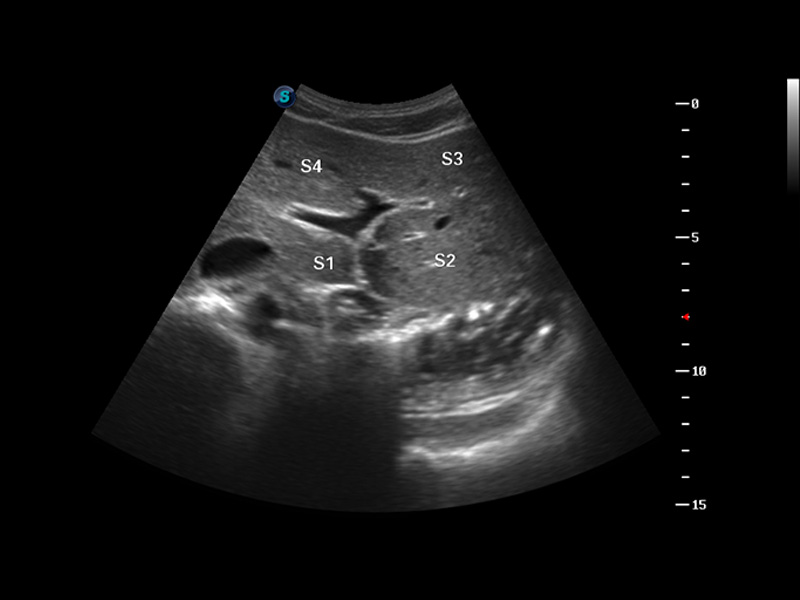

S8 EXP便携式彩色多普勒超声诊断仪是milan米兰研发的高端全身应用型便携彩超。高通道的VIS平台融合可视化(Visual)、智能化(Intelligent)和人性化(Smart)的特点,配以milan米兰自主研发生产的探头大家族,使您能够快速、准确的获得病人信息,提高工作效率的同时减轻疲劳。

μ-Scan微米成像

谐波成像

空间复合成像

3D/4D成像